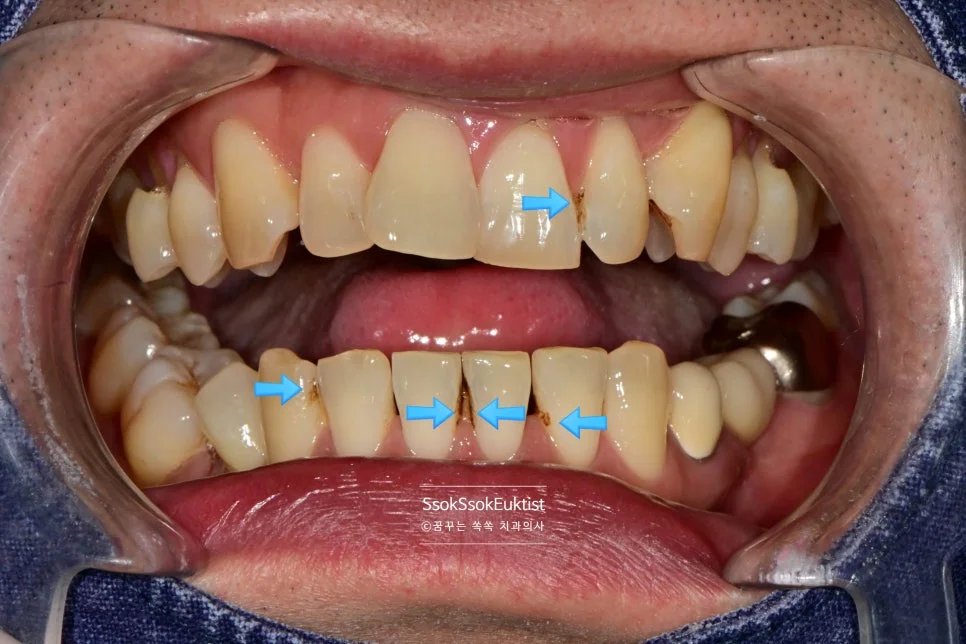

GI 치료 전 — 대부분 V자, 일부 U자 형태

형태를 보면 대부분 V자인데 하나 정도만 U자 형태를 보이고 있습니다. 이런 경우 강한 칫솔질이 치경부 마모증을 악화시켰다고 볼 수 있습니다!

스케일링 + 착색 제거 — 충전 전 깨끗한 상태로 준비

먼저 우리 치과의 자랑인 착색 제거! 스케일링과 동시에 지저분한 착색물질 깨끗하게 날려주는 것부터 시작합니다^^

GI를 이용한 치경부 마모증 충전 중

그러고는 GI를 이용해 치경부 마모증을 충전해 주는데요.

어떤가요? GI를 이용한 충전도 꾀나 괜찮나요?

우리 치과에서는 가장 비싸고 심미적인 GI를 사용하고 있습니다^^

한편 그런데 말입니다… 사실 GI의 경우 색상이 거진 정해져 있어 치아가 GI의 색과 유사한 색이면 이렇게 예쁘게 치료가 가능하고, 치아가 보다 밝거나 어두우면 색상이 좀 안 맞아질 수 있습니다^^